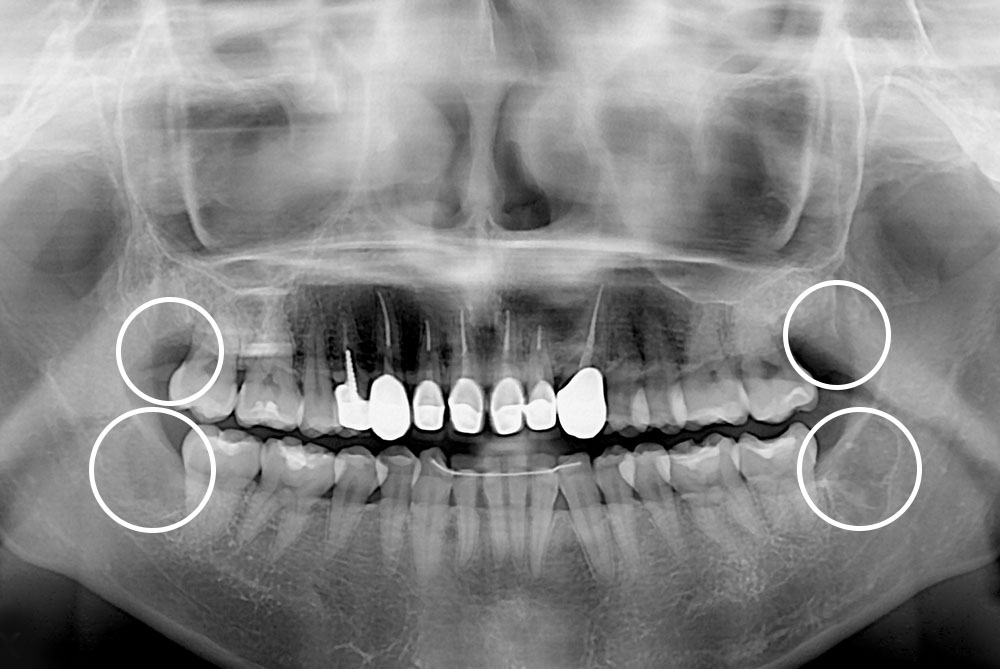

[사랑니] 매복 사랑니 발치

치료후 : 2019-10-17